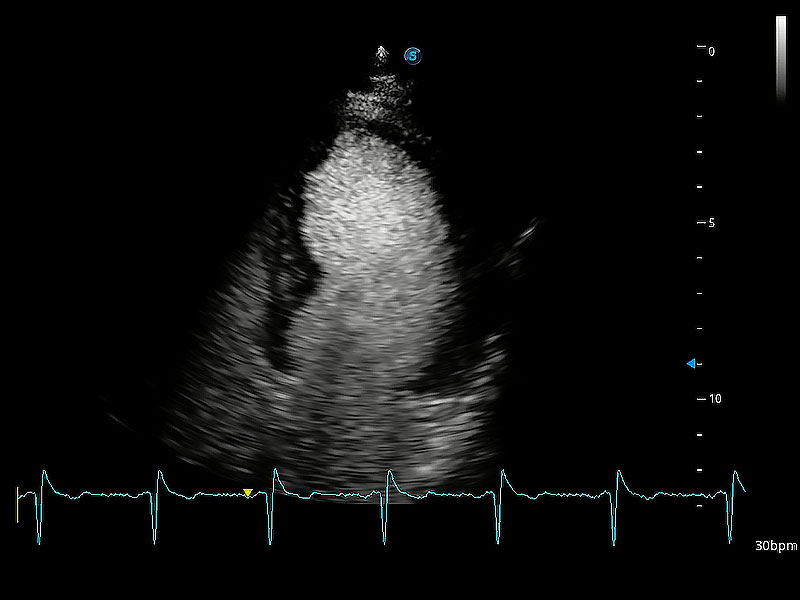

能夠基于左心室壁追蹤和辛普森法,自動(dòng)計(jì)算射血分?jǐn)?shù),支持多個(gè)可移動(dòng)點(diǎn)描跡,與手動(dòng)測(cè)量相比,極大節(jié)省了動(dòng)物醫(yī)生的時(shí)間和精力。